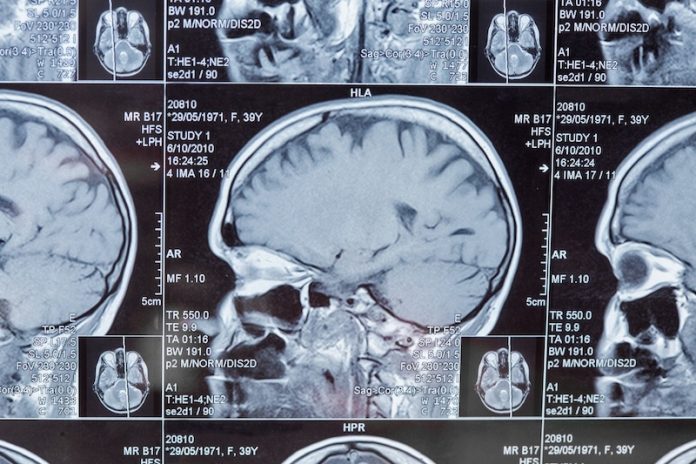

The team used a new kind of MRI scan that looks at how water molecules move within the brain’s gray matter. This technique can detect very small changes in brain tissue.

When water molecules spread more freely, it often means that the tissue is damaged. The major breakthrough is that this method can reveal brain damage even before the brain begins to shrink—a process called brain atrophy—or before any memory or behavior issues appear.

The study found that this new imaging method is more sensitive than traditional brain scans that measure the thickness of the brain’s cortex. For people with a mutation in the C9orf72 gene—one of the genes linked to FTD—researchers could spot early brain changes even before symptoms began.